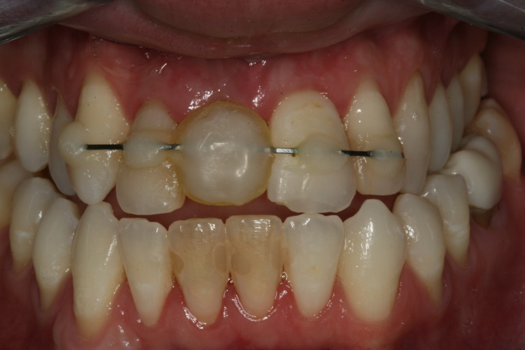

Case 3. TRAUMA: SINGLE Central INCISOR-GUIDED Smile

A 23-year-old man reported to the dental practice on January 3. Apparently, while on vacation and celebrating the New Year, the patient experienced a loss of equilibrium and found himself horizontal in the crosswalk. When surveying the damages, his friends noticed he was missing tooth No. 8. Those who were involved were not able to find the missing maxillary central incisor. The young man was eventually seen about 3 days after the trauma. A CBCT radiograph, study models, and photographs were collected, and teeth Nos. 6 through 10 were immobilized with composite and 20 x 20 orthodontic wire (Figure 14). The CBCT and photos were emailed to the dental laboratory, and the analog intraoral impression with a centric occlusion bite registration was sent via ground transportation. Due to the nature of the trauma, the laboratory and the author expeditiously converted the analog diagnostics and merged all the patient's data sets to develop the plan. Based on the 3D data sets, the laboratory and the dentist were able to accurately assess the volume of bone and soft tissue remaining after the trauma. The volume was still intact and soft tissue was plentiful (Figure 15 and Figure 16).

The decision was to develop a surgical guide, place the implant, and fabricate a screw-retained one-piece non-engaging abutment with a slender emergence profile and a polymethyl methacrylate (PMMA) provisional. Ten days after the trauma, the patient was seen in the dental office for the placement of the dental implant. On the day of surgery, a 3D-printed surgical guide was used, developed from the CBCT radiograph and the digitized impressions (Figure 17 and Figure 18).

Fig 14. Immobilization splint placed 3 days after trauma.

Figure 14

Fig 15. Surgery was planned for 10 days after the trauma incident.

Figure 15

Fig 16. Preoperative periapical radiograph on the day of surgery.

Figure 16